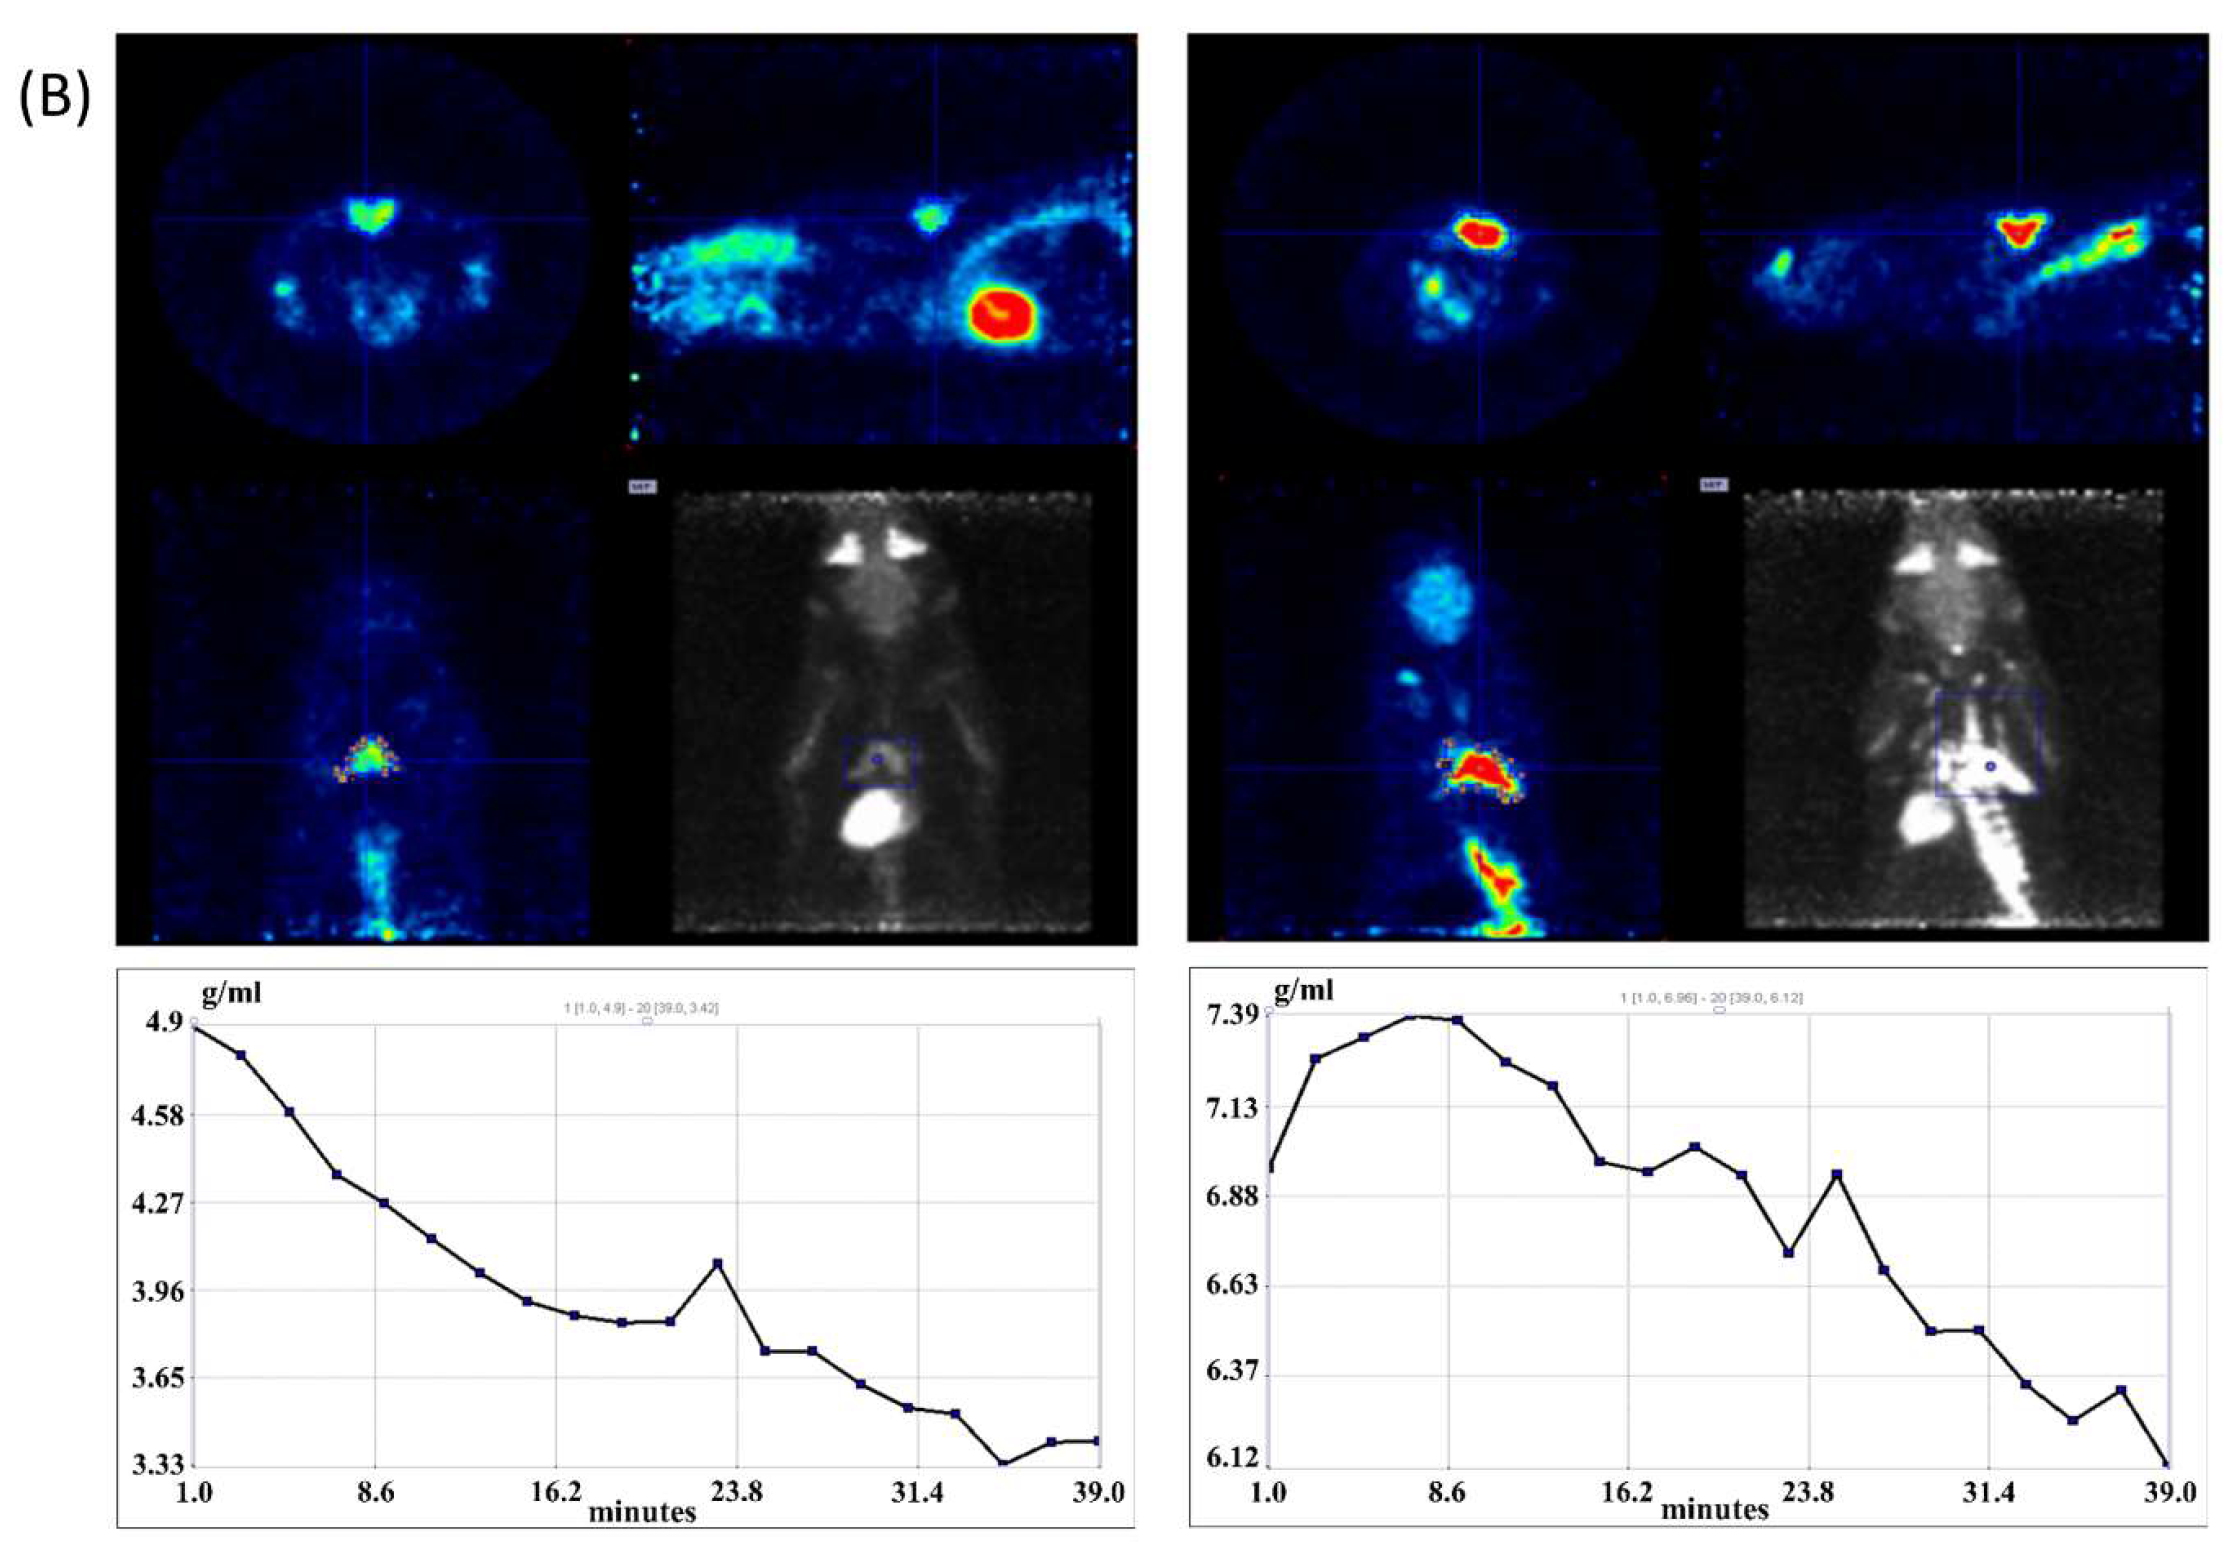

2.5. 18F-FDG-microPET Imaging

3.2. iBAT Functioning of 5HT Sublines in Conditions of Experimentally Induced Thermogenesis